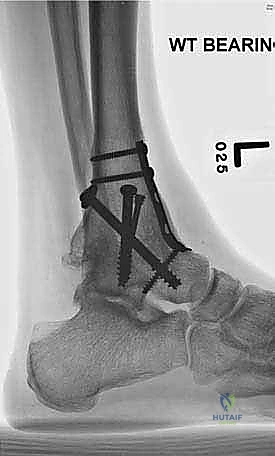

- الأشعة السينية أثناء الوقوف (Weight-bearing X-rays): هي الفحص الذهبي والأهم. يجب أن تؤخذ الأشعة والمريض واقف لتحمل الوزن. تظهر الأشعة تضيق المسافة المفصلية (دليل على فقدان الغضروف)، وجود نتوءات عظمية، تصلب العظم، وأي انحراف في محور المفصل.

| طرق العلاج | أدوية مضادة للالتهابات (NSAIDs)، أحذية طبية مخصصة (Rocker-bottom shoes)، دعامات الكاحل (AFO)، حقن الكورتيزون أو البلازما (PRP)، العلاج الطبيعي. | جراحة إزالة الغضاريف التالفة ودمج العظام (Arthrodesis) باستخدام مسامير وألواح معدنية. |

- تثبيت ميكانيكي حيوي أقوى: يتيح المدخل الأمامي وضع شريحة معدنية (Anterior Plate) على الجانب الأمامي للمفصل. من الناحية الميكانيكية الحيوية (Biomechanics)، يعتبر الجانب الأمامي هو "جانب الشد" (Tension side) أثناء المشي. وضع الشريحة هنا يوفر تثبيتاً فائق القوة ويقلل من معدلات عدم الالتئام.

- التخطيط الجراحي الرقمي: باستخدام صور الأشعة المقطعية، يقوم الدكتور هطيف بتخطيط الجراحة على الكمبيوتر لاختيار حجم المسامير والشرائح المناسبة بدقة مليمترية.